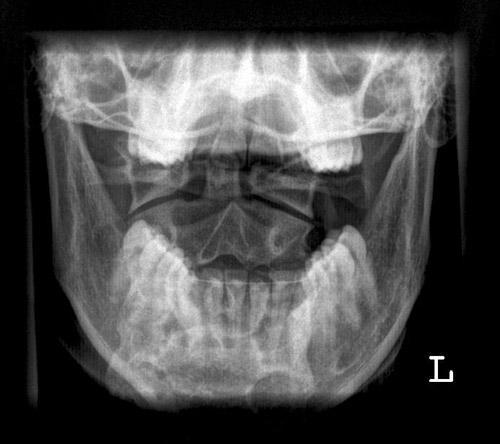

Dens a.p.

Fehler

Überlagerung des Atlas und der Densspitze durch die Hinterhauptschuppe. Die Bissfläche der Zähne des Oberkiefers bilden sich weit oberhalb der Densspitze ab.

Abhilfe

Kinn geringfügig stärker gegen den Hals anziehen lassen.